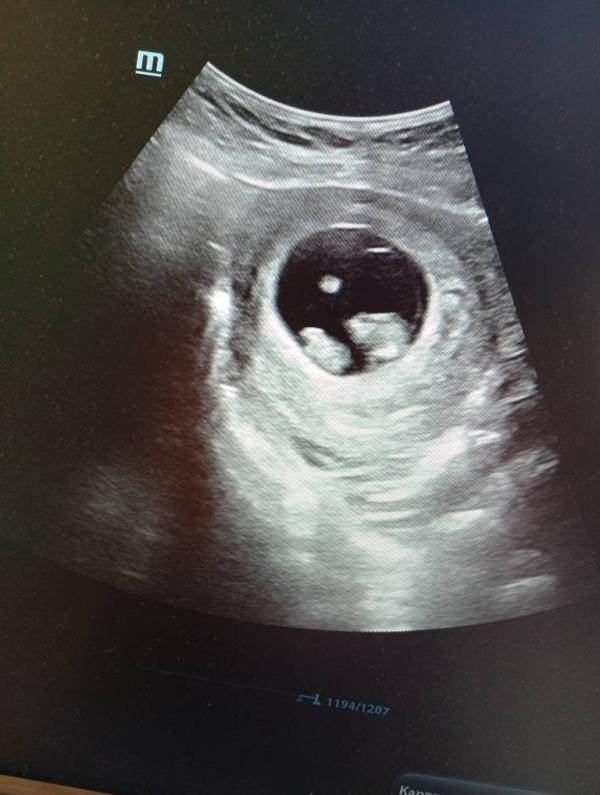

Полина·Мама двоих (3 года, 6 лет), ждёт третьего

Девочки это двойня?

Ну на этом сроке уже и сердцебиение должно быть

Врач должен был послушать 2 сердечка, и вообще сказать двойня у вас или нет